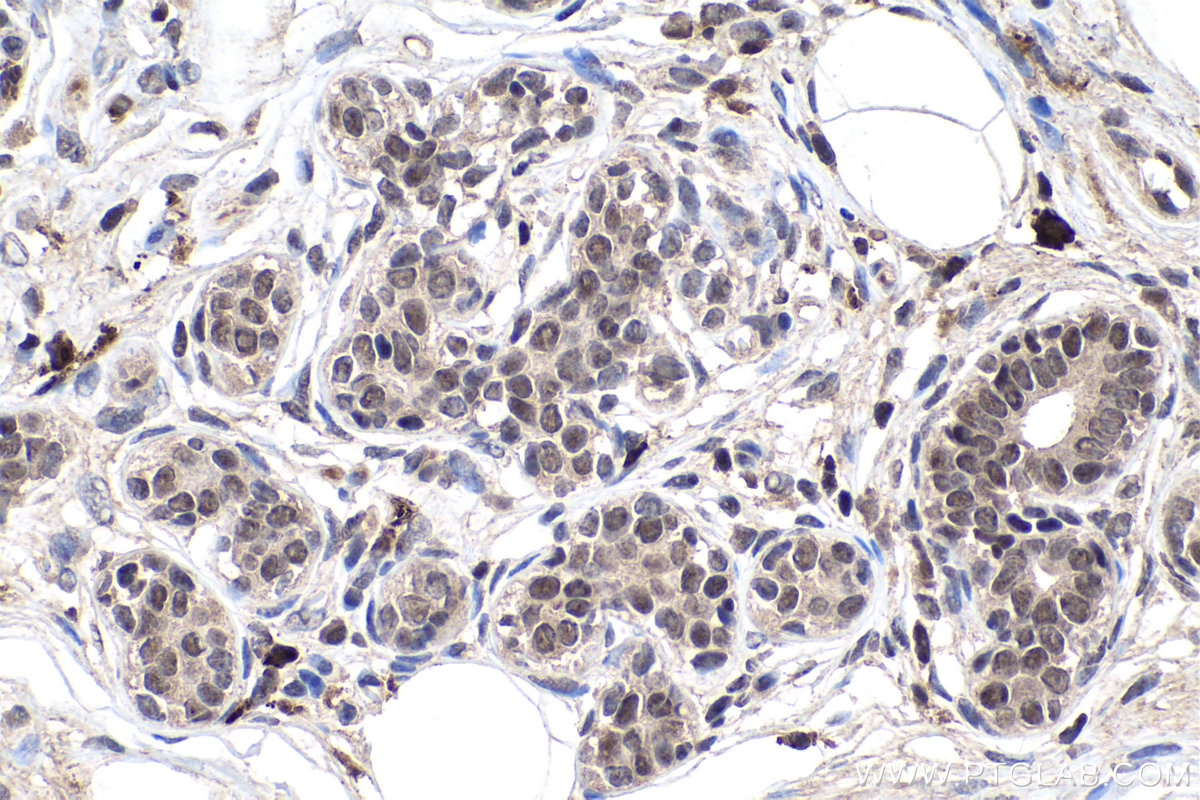

| Positive IHC detected in | human breast cancer tissue, human cervical cancer tissue, mouse testis tissue Note: suggested antigen retrieval with TE buffer pH 9.0; (*) Alternatively, antigen retrieval may be performed with citrate buffer pH 6.0 |

| Immunohistochemistry (IHC) | IHC : 1:2000-1:8000 |